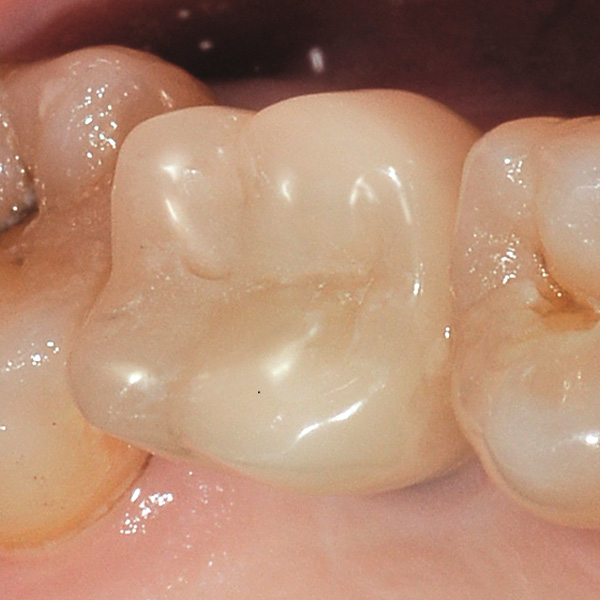

Reconstrucción de corona implantosoportada de cerámica híbrida VITA ENAMIC multiColor

Sobre todo las restauraciones sobre implantes están sometidas a elevadas solicitaciones. Tras la extracción y el implante, al paciente le falta el tejido fibroso elástico del lecho dental natural. En consecuencia, no se absorben las fuerzas oclusales, sino que se transmiten directamente a la restauración, al implante, al hueso y a los dientes antagonistas. La cerámica híbrida VITA ENAMIC incorpora una matriz dual de cerámica (86 % del peso) y polímero (14 % del peso). Esto le otorga una elasticidad similar a la de la dentina y la capacidad de absorber fuerzas oclusales. Gracias a su elevada dimensión vertical, la pieza en bruto policroma VITA ENAMIC multiColor en la geometría EMC-16 posibilita, incluso en caso de hueso atrofiado, la confección de coronas sobre pilar monolíticas de una pieza. El doctor y catedrático Alexander Hassel muestra en el siguiente artículo cómo ha tratado a una paciente empleando este método de restauración.